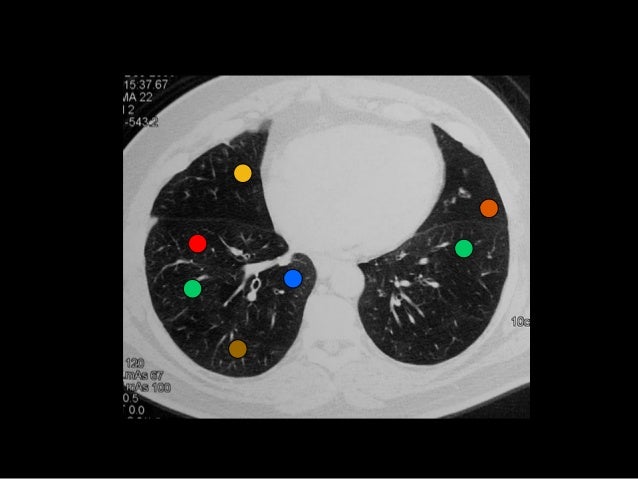

This diagram may help simplify the segmental anatomy of the lung and the pulmonary arteries. A bronchopulmonary segment is a portion of lung supplied by a specific segmental bronchus and arteries. 1 study figure s1 1.

The right upper lobe has apical posterior and anterior segments middle lobe has medial and lateral segments and the lower lobe has superior apical and 4 basal segments anterior medial posterior and lateral. We will learn the anatomy of the tracheobronchial tree and the segments together. Each segment is supplied by its own bronchus which is called a segmental bronchus.

Knowledge of bronchopulmonary segment anatomy is important for understanding and interpreting radiographs and other medical images of the lungs especially when needed as reference for surgical resection of diseased lung segments. Each lung is divided into lobes and each lobe is divided into segments. But when churchill in 1939 successfully removed a segment of the lower lobe for bronchiectasis a new emphasis was created.